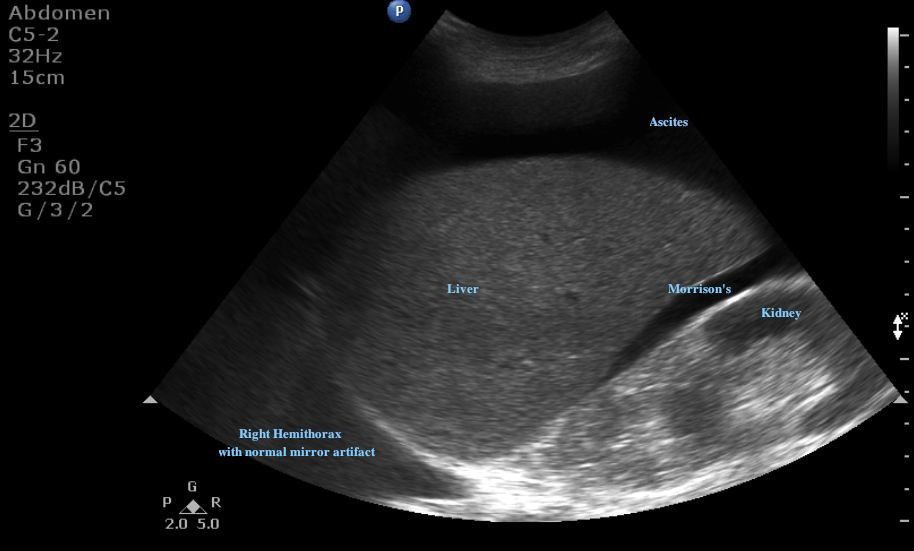

Ultrasound for Paracentesis Ultrasound Cases Info Air Pocket In Liver pneumobilia is typically seen as linear branching gas within the liver most prominent in central large caliber ducts as the flow of bile pushes. Pneumobilia is usually characterized by the presence. Pneumobilia usually can be distinguished from air in the portal venous system by its appearance on computed tomography (ct) scan. pneumobilia is caused when an air bubble. Air Pocket In Liver.